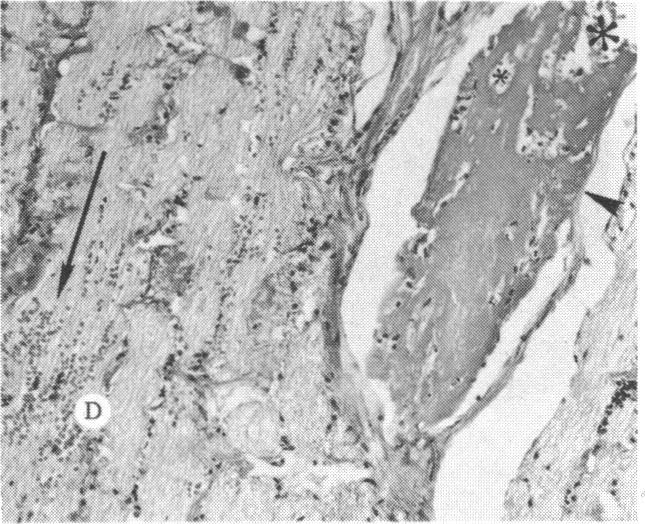

The clinical and histopathologic features of 29 eyes from 29 patients with central retinal vein occlusion (CRVO) are reported. A fresh or a recanalized thrombus was observed in each eye. This study considers the temporal aspects of the cases, and it notes the different morphologic features of the occlusion. These observations explain most of the variability of the changes observed in previous reports. We believe that these different features represent the various stages in the natural evolution of such a thrombus. The interval between CRVO and histopathologic study in our series ranged from six hours to more than 10 years. Local and systemic factors were reviewed and were found to be important in the pathogenesis of thrombus formation. Local diseases with a predisposing effect on CRVO included: glaucoma, papilledema, subdural hemorrhage, optic nerve hemorrhage, and drusen of the optic nerve head. Associated systemic diseases included: hypertension, cardiovascular and cerebrovascular disease, diabetes mellitus, and leukemia with thrombocytopenia. A fresh thrombus in the CRVO was observed in three (10.3%), and a recanalized thrombus in 26 eyes (89.7%). Endothelial-cell proliferation was a conspicuous feature in 14 (48.3%) of the eyes. Chronic inflammation in the area of the thrombus, and/or vein wall or perivenular area was observed in 14 (48.3%) of the eyes. Arterial occlusive disease was observed in seven eyes (24.6%). Cystoid macular edema was found in 26 (89.7%) of the eyes.

报告了29例视网膜中央静脉阻塞(CRVO)患者29只眼的临床和组织病理学特征。每只眼中均观察到新鲜或再通的血栓。本研究考虑了病例的时间因素,并记录了阻塞的不同形态学特征。这些观察结果解释了先前报告中观察到的变化的大部分变异性。我们认为这些不同特征代表了此类血栓自然演变的各个阶段。我们系列中CRVO与组织病理学研究之间的间隔时间从6小时到10多年不等。对局部和全身因素进行了回顾,发现它们在血栓形成的发病机制中很重要。对CRVO有 predisposing 作用的局部疾病包括:青光眼、视乳头水肿、硬膜下出血、视神经出血和视神经乳头玻璃膜疣。相关的全身疾病包括:高血压、心血管和脑血管疾病、糖尿病以及伴有血小板减少的白血病。在CRVO中观察到3只眼(10.3%)有新鲜血栓,26只眼(89.7%)有再通血栓。14只眼(48.3%)中内皮细胞增殖是一个显著特征。14只眼(48.3%)中观察到血栓区域、和/或静脉壁或静脉周围区域有慢性炎症。7只眼(24.6%)中观察到动脉闭塞性疾病。26只眼(89.7%)中发现黄斑囊样水肿。 (注:文中“predisposing”可能是“易患的”意思,但在专业医学语境中,可能有更准确特定含义,这里按常见理解翻译,具体含义需结合医学专业知识进一步确认。)